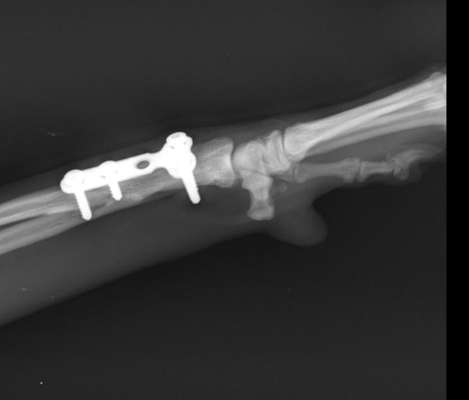

Hallo liebe Community, unserer Hündin Terika (ca. 5 Jahre) muss leider die Metallplatte aus der linken Pfote entfernt werden. Sie ist jetzt 3 Jahre bei uns und knickte jetzt vermehrt mit der Pfote beim Laufen immer weg. Die Platte muss ihr damals in Kroatien schon gesetzt worden sein. Dies hatten wir auch nur durch Zufall festgestellt. Nun meine Frage: hat jemand schon Erfahrungen mit solch einen Eingriff gemacht? auf was können wir uns so einstellen? Schonen und Kragen? Freu mich über eure Rückmeldungen.

Um die Platte zu entfernen wird Terika einer Operation unterzogen. Hierbei wird die Haut im Bereich des Implantats eröffnet und das Muskelgewebe bis zum Knochen freipräpariert. Anschließend wird das Implantat aus dem Knochen entfernt. Nach Entfernung des Implantats wird die eröffnete Haut durch eine Naht verschlossen. Je nach Möglichkeit erhält Terika einen Verband, oder die Naht wird nur durch ein Pflaser geschützt. Egal, welche Variante angewandt wird, ist es sehr wichtig, dass Terika nicht an der Wunde leckt oder knabbert. Um dies sicher zu verhindern, sollte Terika bis zum Ziehen der Fäden 12-14 Tage nach Operation zur Sicherheit Tag und Nacht einen Halskragen tragen.

Nach der Operation sind in dem Bereich, in dem die Schrauben des Implantats saßen, kleine Löcher im Knochen. Diese stellen für aber gewöhnlich kein Problem dar und der Knochen hat in der Regel eine ausreichende Stabilität. Die Löcher wachsen nach einigen Wochen zu. Dennoch ist es sinnvoll, Terika in den ersten Tagen ruhig zu halten und nur kontrolliert an der Leine zu bewegen. Die Stabilität des Knochens kann nach Entfernung der Implantate nochmal genau beurteilt werden. Dein Tierarzt/deine Tierärztin kann dir nach Entfernung eine Einschätzung geben, ob eine Ruhighaltung über einige Tage notwendig ist.